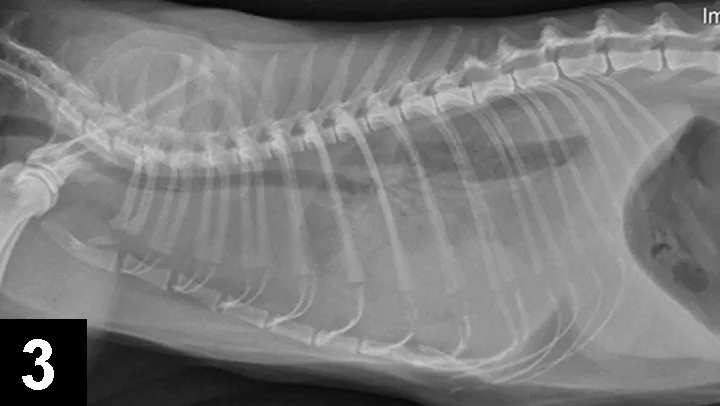

Many illnesses and injuries can impact normal oxygenation and ventilation. Stress, anxiety, and forced activity should be minimized. Pleural space disease (eg, pneumothorax, hemothorax, hydrothorax, pyothorax, chylothorax) can be identified by tachypnea, dull lung sounds with thoracic auscultation, open-mouth breathing, and a dyssynchronous respiratory pattern (ie, opposite motion of the chest and abdomen). Radiographs can identify pleural space disease (Figures 2 and 3) but should not be performed in cases with severe respiratory difficulty. If available, a quick ultrasound of the chest (thoracic-focused assessment with sonography for trauma [TFAST]) can readily identify pleural effusion and can be much less stressful and time consuming than radiography. Supplemental oxygen and thoracocentesis are always indicated.

Figure 3. Right lateral radiograph of a cat with hydrothorax secondary to heart disease. Note the loss of the cardiac silhouette and lack of normal lung fields.